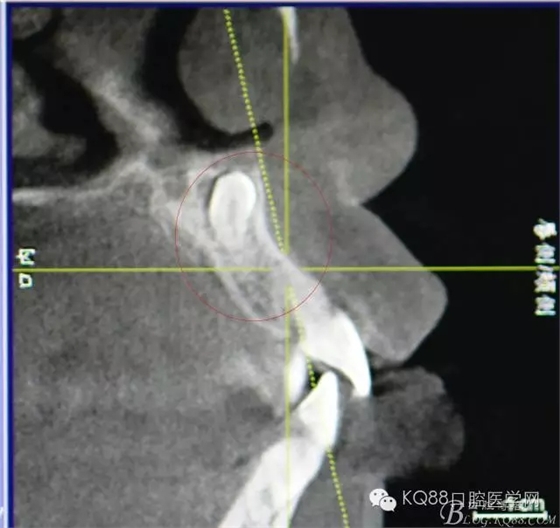

圖2.CBCT矢狀面影像檢查:多生牙牙冠上方與鼻底僅有黏膜相隔

圖3.CBCT三個方向剖面圖影像:多生牙牙根阻擋11內收、牙冠接近鼻底

圖4.cbct的三維重建影像:多生牙牙尖幾乎和鼻底相通